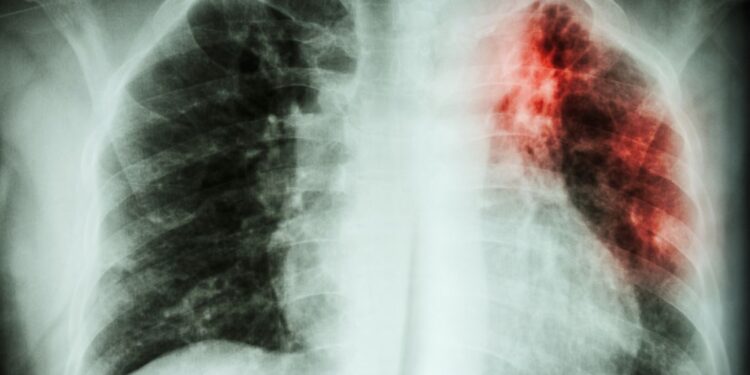

Sono stati presentati nuovi studi per migliorare e stabilizzare i valori di funzionalità ventilatoria e diffusione del monossido di carbonio dei pazienti affetti da fibrosi polmonare idiopatica. La fibrosi polmonare idiopatica costituisce una patologia respiratoria la cui spettanza di vita oscilla in media fra i 3 ed i 5 anni dal momento della diagnosi, mostrando una prognosi del tutto simile a quella del tumore del polmone, una delle forme di neoplasia a prognosi peggiore. Recentemente è stato inoltre descritto un gruppo eterogeneo di fibrosi polmonari, diverse dalla fibrosi polmonare idiopatica, definite come fibrosi polmonari progressive che presentano una prognosi del tutto simile alla forma idiopatica.